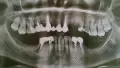

Девять лет назад я потеряла передние зубы. Взяла кредит и поставила металлокерамический мост.

Прошло пять лет и мост начал шататься, откололась керамика на одном зубе. В итоге год назад он выпал. Клеила его как могла. Денег, чтобы поставить другой просто нет. Зубы мудрости разрушились, и затянулись десной. На верхней челюсти почти не осталось зубов.